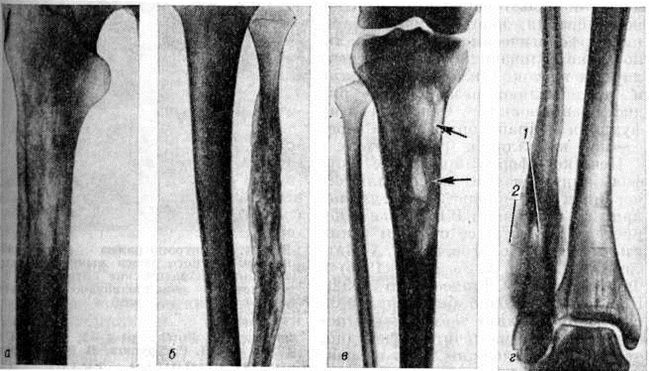

Ретикулосаркома кости первичнаяРетикулосаркома кости первичная (латынь reticulum сетка саркома; синонимы: моноцитома кости, ретикулоклеточная саркома кости) — солитарное злокачественное новообразование кости ретикулярно-клеточного происхождения. Локализуется обычно в длинных трубчатых костях, реже возникает в плоских костях или других отделах скелета. Впервые выделена как нозологическая форма в 1939 год Паркером и Джексоном (F. Parker, Н. Jackson). Ретикулосаркома кости первичная составляет около 3% всех первичных опухолей скелета. Чаще заболевают лица мужского пола в возрасте 15—30 лет. Этиология неизвестна. Описаны случаи возникновения Ретикулосаркома кости первичная на основе болезни Педжета (смотри полный свод знаний: Педжета болезнь). Первоначально опухоль всегда расположена внутрикостно с последующим частичным или полным разрушением компактного вещества. Опухоль представлена очагом мягкой серо-розовой ткани, не имеющим чётких границ. Сравнительно часто при Ретикулосаркома кости первичная в зоне очага поражения наблюдается патологический перелом с признаками вторичного репаративно-реактивного остеогенеза. Микроскопически основным структурным элементом являются опухолевые клетки лимфоидно-ретикулярного типа с более или менее выраженными признаками полиморфизма и атипии с овальными, бобовидными или подковообразными ядрами и достаточно чётко контурированной цитоплазмой (рисунок 1, а), Клетки Ретикулосаркома кости первичная по размерам несколько крупнее клеток саркомы Юинга (смотри полный свод знаний: Юинга опухоль). Иногда клетки содержат два или три ядра, обычно с хроматином в виде грубых неправильной формы глыбок. Часто наблюдаются фигуры митоза. В отличие от опухоли Юинга в Ретикулосаркома кости первичная почти постоянно удаётся выявить богатую сеть аргентофильных волокон, которые иногда оплетают почти каждую клетку (рисунок 1, б), В цитоплазме клеток Ретикулосаркома кости первичная не содержится гликоген. В периферических отделах опухоли часто наблюдаются признаки коллагенообразования иногда вплоть до формирования небольших фиброзных полей. В этих же участках опухоли можно видеть и очаги реактивного остеогенеза. Клинически заболевание отличается постепенным началом. Первыми симптомами являются боли в зоне очага поражения с иррадиацией вдоль нервных стволов по типу неврита или корешковых болей. Вначале боли интермиттирующие, иногда возникают только при физической нагрузке и лишь через несколько месяцев приобретают постоянный характер. В некоторых случаях боли локализуются в ближайшем к очагу поражения суставе. Часть больных (около 30—40%) обращается за медпомощью уже при наличии патологический перелома. Поэтому воспалительные и реактивные изменения нередко затрудняют диагностику. Ретикулосаркома кости первичная в 20—25% случаев метастазируют в костную систему, чаще всего в плоские кости черепа, лопатку, кости таза и ребра. Диагноз устанавливают с помощью комплексного клинического, рентгенологическое, радиоизотопного и морфологический исследования. Рентгенологические картина многообразна и зависит от фазы роста и локализации опухоли. Вначале появляется участок деструкции мелкозернистой, пористой, пятнистой структуры, который расположен в губчатом веществе (рисунок 2, а). В дальнейшем нарастает литический процесс, формируются очаги деструкции округлой или овальной формы с нечёткими очертаниями. Часто наблюдается несоответствие между мало выраженной клинические, симптоматикой и значительными рентгенологическое изменениями. Это обусловлено инфильтративным ростом опухоли, образованием внекостного её компонента, который не содержит известковых включений. Может выявляться пластинчатая деструкция компактного вещества (рисунок 2, б). Деструктивный процесс иногда характеризуется наличием крупных опухолевых узлов с плотными краями и различной степени «вздутием» кости, напоминающим костную кисту, а при наличии большого количества перекладин — остеобластокластому (рисунок 2, в, г). |

Эндостальная реакция может быть в виде склеротической каёмки на границе крупного очага деструкции или очагового уплотнения при мелкоочаговой деструкции. Очень редко встречается резкое уплотнение кости, при котором костно-мозговой канал не дифференцируется.

Деструктивные изменения сопровождаются разнообразной периостальной реакцией — слоистым, кружевным, бахромчатым и спикулообразным периостозом. Линейный периостит является ранним симптомом, выявляющимся до распространения опухоли в мягкие ткани.